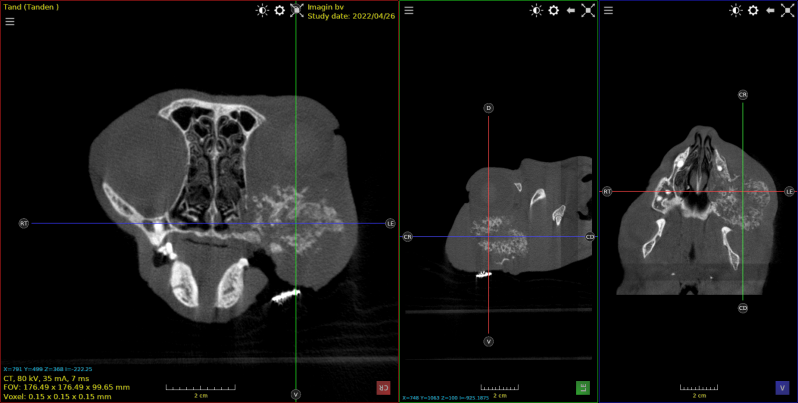

Hond Fila braziliero , van 7 maanden met tandwortel abces .

Gedeelte van het bot rond de tandwortel was aangetast .